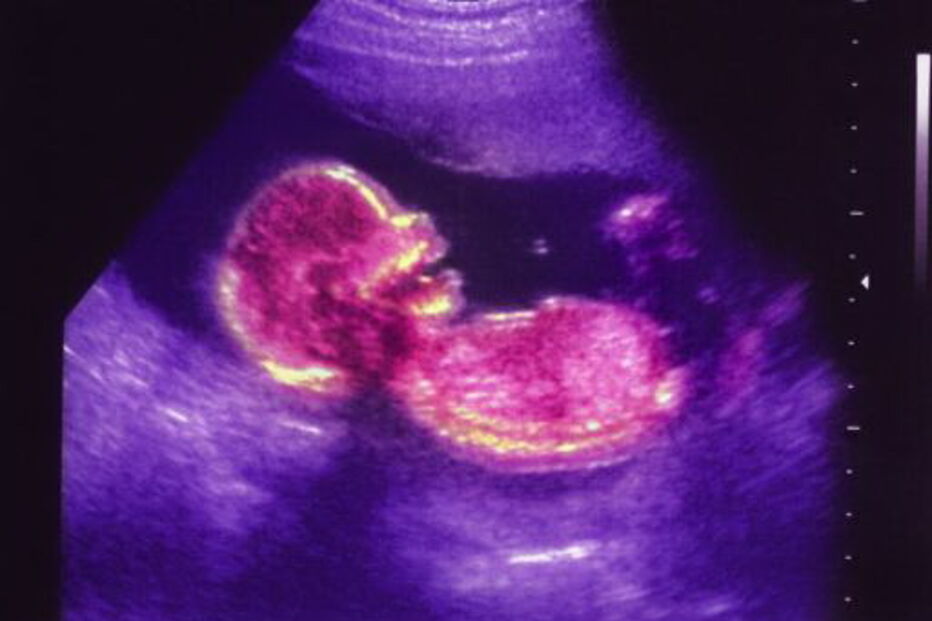

Investigadores da Universidade de Harvard, Estados Unidos, descobriram como durante a gravidez o sistema imunitário protege o feto de infeções sem destruir as células infetadas, algo nunca antes observado.

"Demonstrámos que as células natural killer da decídua humana (zona onde a placenta invade o útero), que são as células imunitárias do útero mais abundantes durante o primeiro trimestre da gravidez, têm a capacidade de eliminar infeções bacterianas dentro de células da placenta, sem matar essas mesmas células", e fazem-no formando um pequeno tubo entre si e a célula da placenta, injetando assim a granulisina na célula infetada, explicam os investigadores.

E frisam que esse mecanismo imunológico de eliminar uma infeção intracelular sem matar a célula infetada "nunca tinha sido observado antes" e que é isso que permite ao sistema imunitário manter a tolerância ao feto ao mesmo tempo que o protege de infeções.